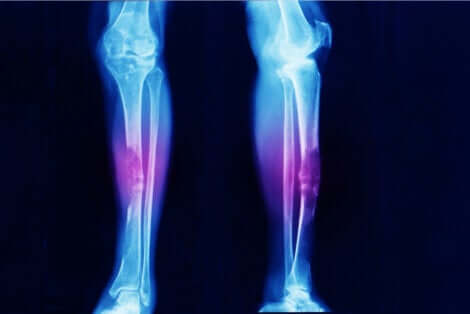

- Osteosarcoma: cancro delle ossa.